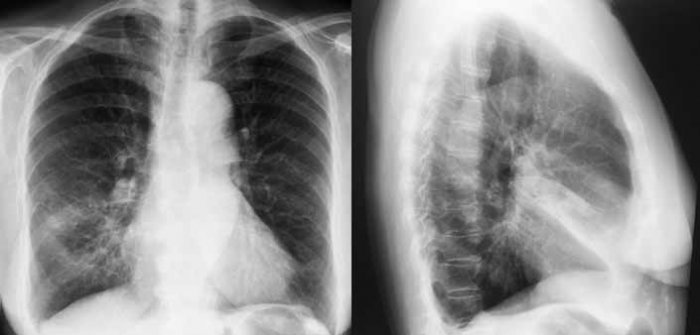

Представлен клинический случай эффективного применения интрапульмональной перкуссионной вентиляции у пациентки 75 лет с ателектазом средней доли, который развился на фоне внебольничной пневмонии. В амбулаторных условиях использовался преимущественно аппарат НС (Percussionaire® Corporation, США). Динамика разрешения ателектаза подтверждена динамическими исследованиями органов грудной клетки с использованием компьютерной томографии.

Приводится клиническое наблюдение.